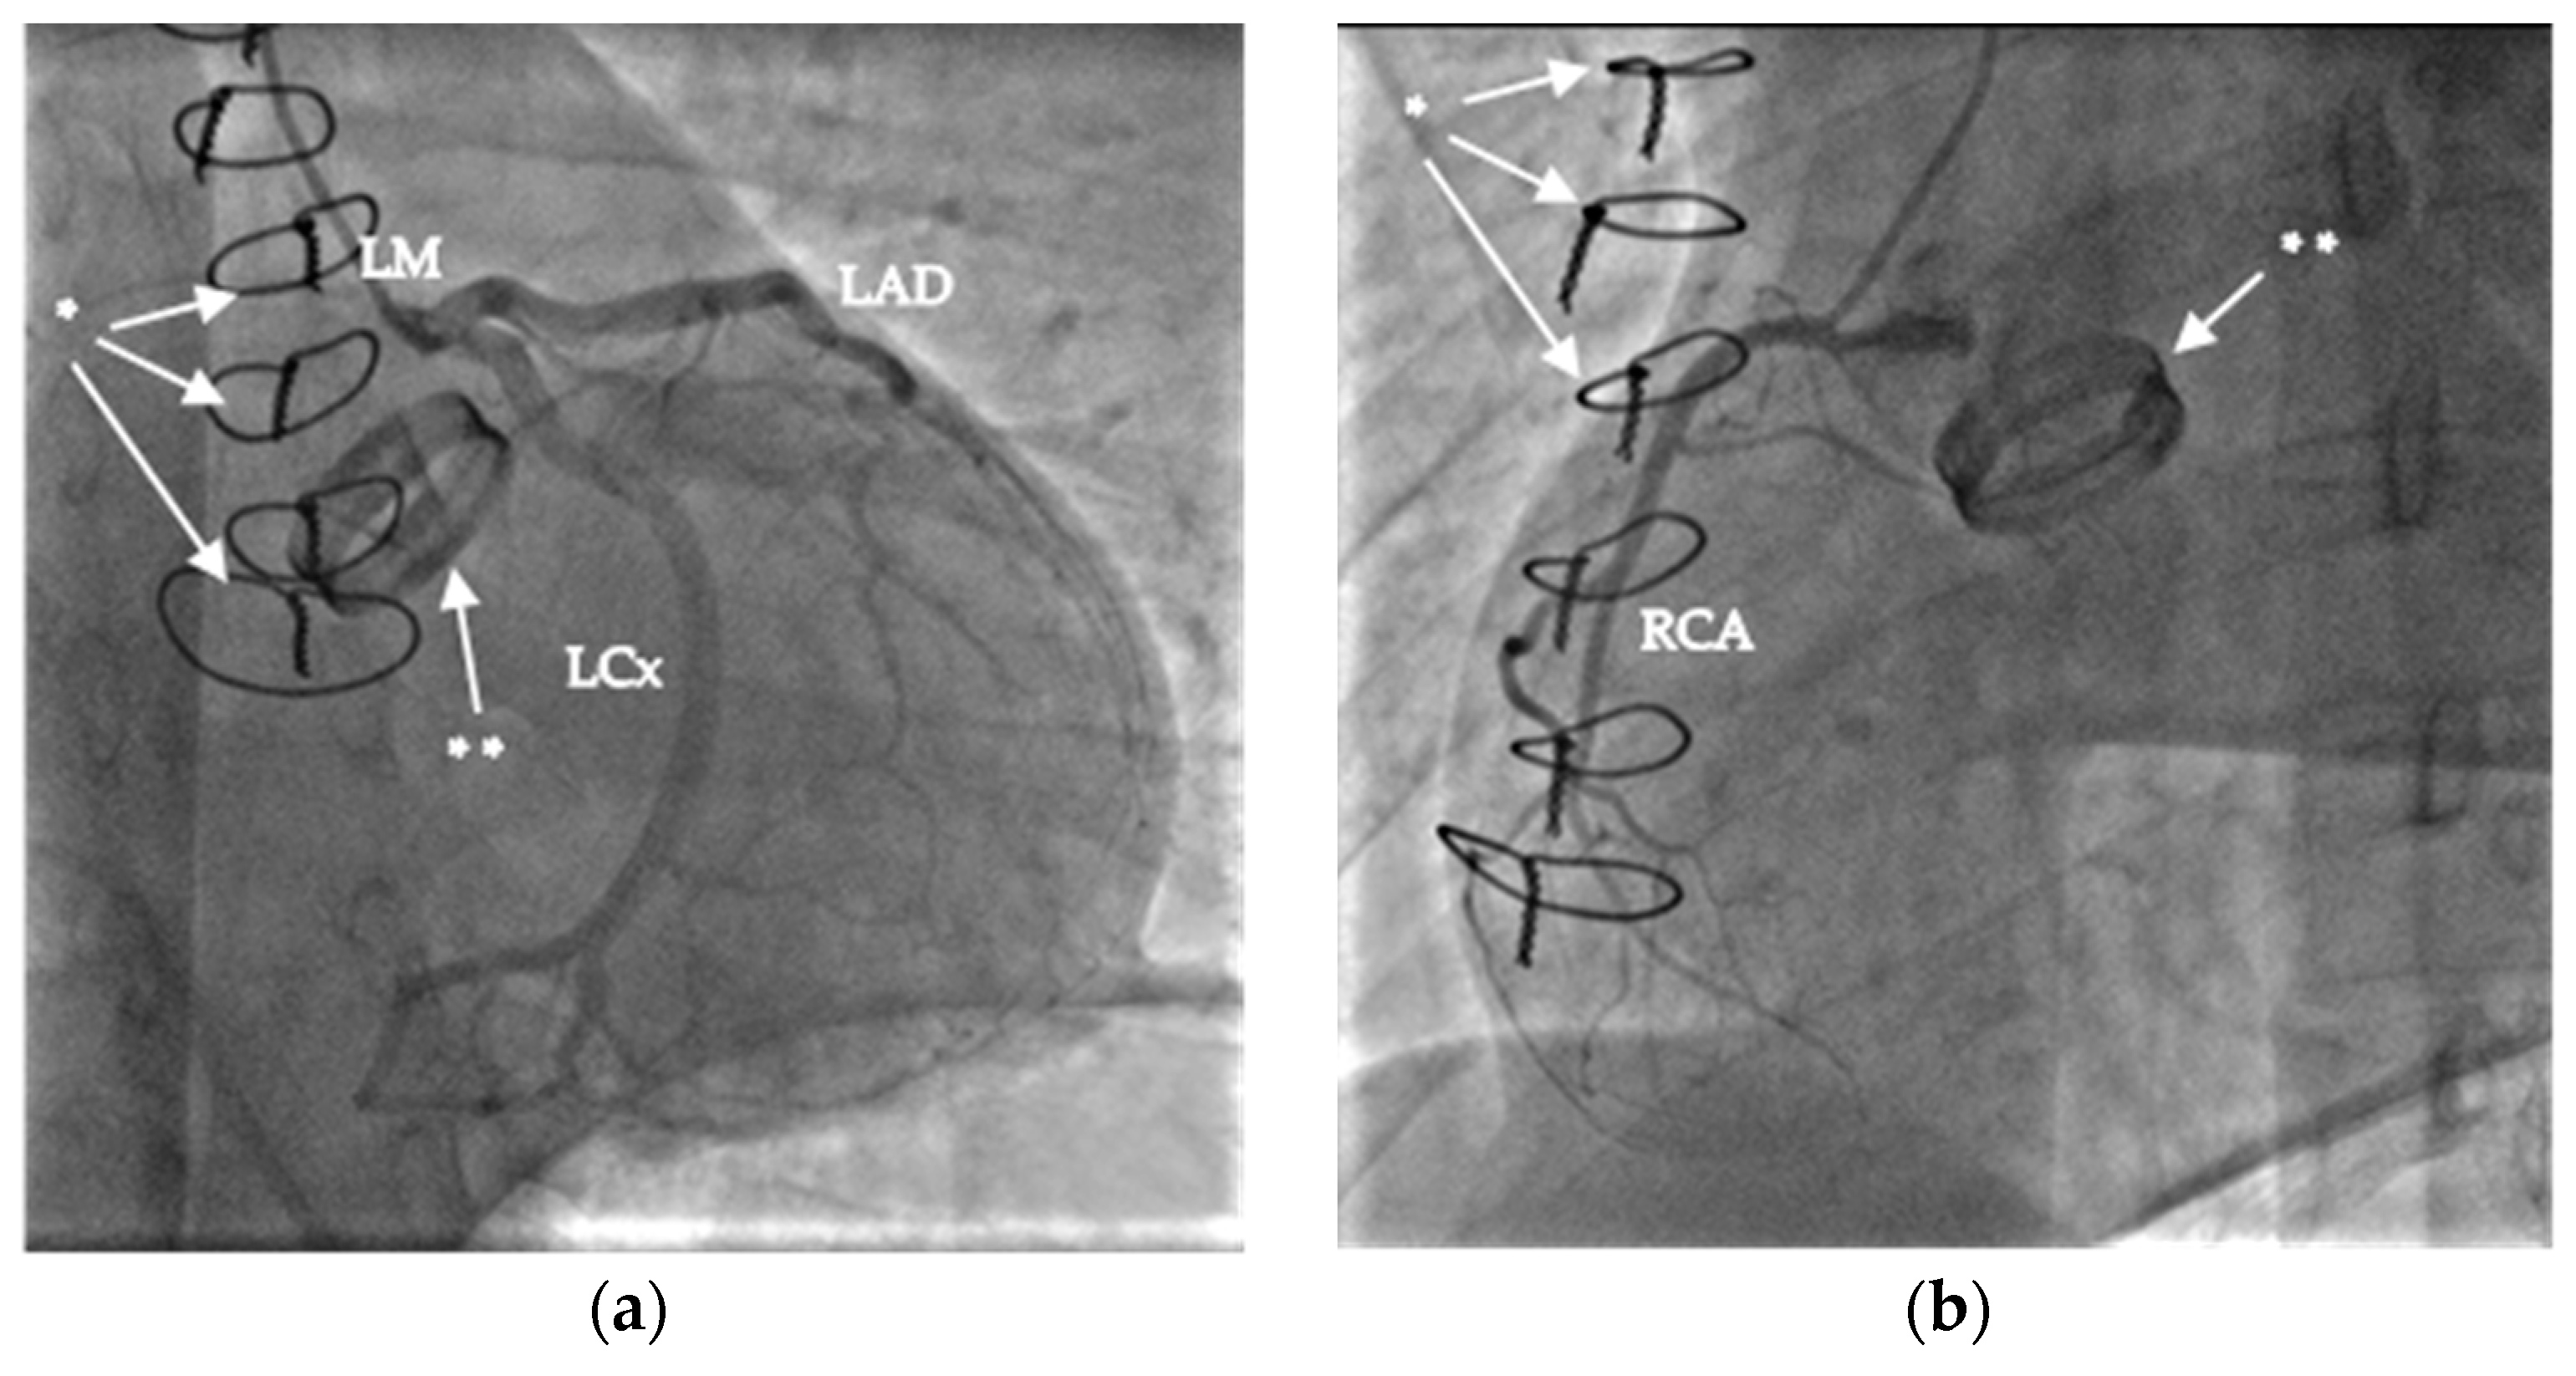

| 19:34 | immediate coronary angiogram, negative result | |